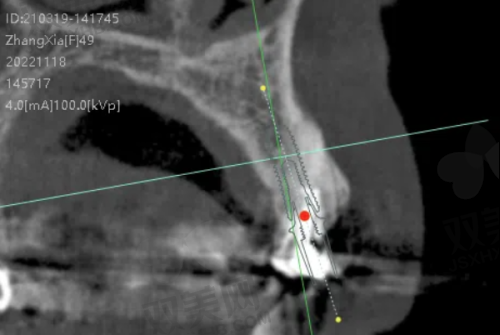

北京昌平牙适乐口腔门诊部的技术特点十分显著。在诊断方面,门诊部引进了精良的口腔CT等设备,能够正确地获取患者口腔的三维信息,为医生制定治疗方案提供严谨的数据支持。在治疗技术上,门诊部紧跟国内外口腔医学发展趋势,不断引进和应用新技术、新材料。例如,在牙齿矫正方面,采用隐形矫正技术,具有美观、舒适、可摘戴等优点,大大提高了患者的矫正体验;在牙齿种植方面,运用微创种植技术,减少了手术创伤,缩短了修复时间。此外,门诊部还注重技术创新和人才培养,定期组织医生参加学术交流和培训活动,不断提升医生的技术水平和服务能力。